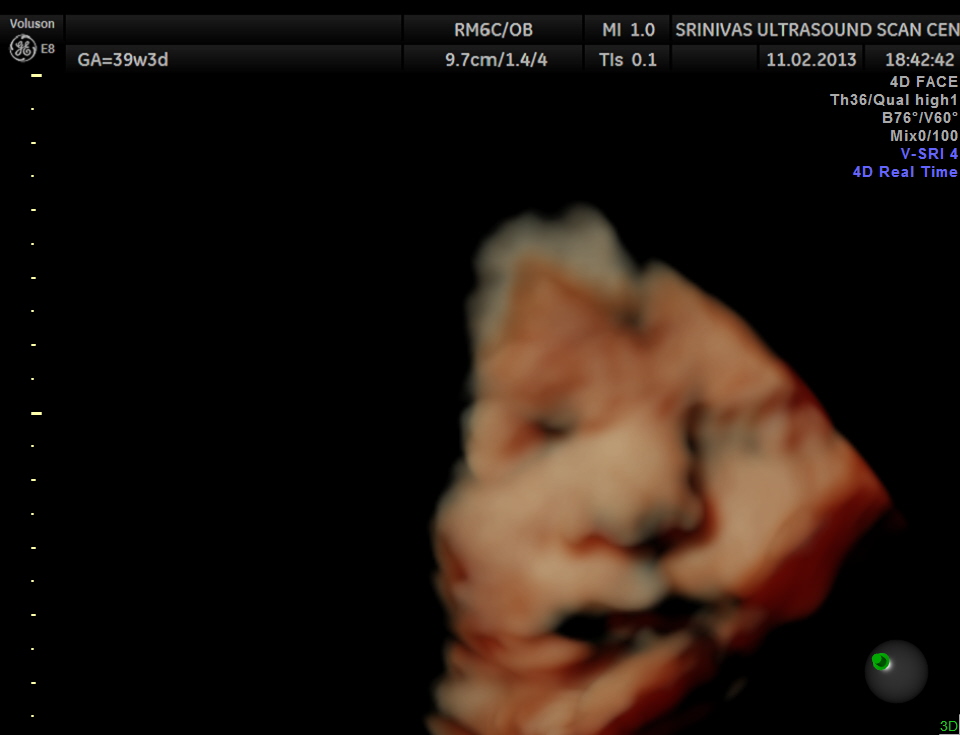

This was a 22 year old lady in her 38th week of gestation, sent for 2nd opinion to confirm cleft lip.

These images are presented to show the usefulness of 3 d reconstruction in demonstrating the face and the anomalies .

The 1st picture shows the cleft lip clearly. But the reconstructed images are self explanatory